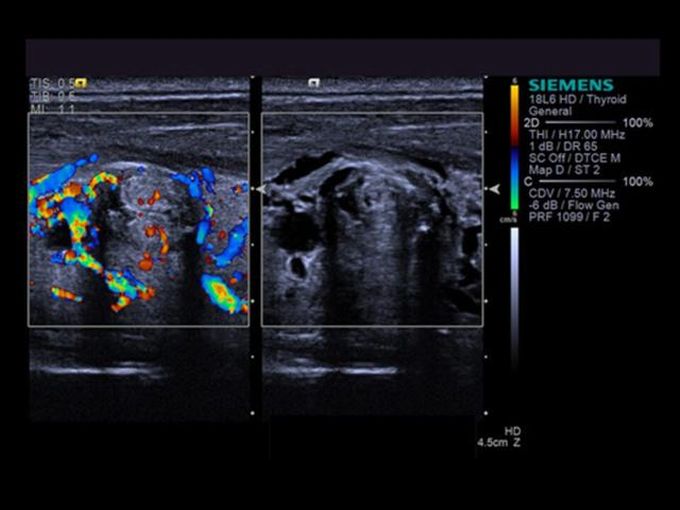

Кроме новой техники, можно заказать восстановленные медицинские системы: ультразвуковые сканеры, томографы, флюороскопы, ангиографы и хирургические установки С-дуга.